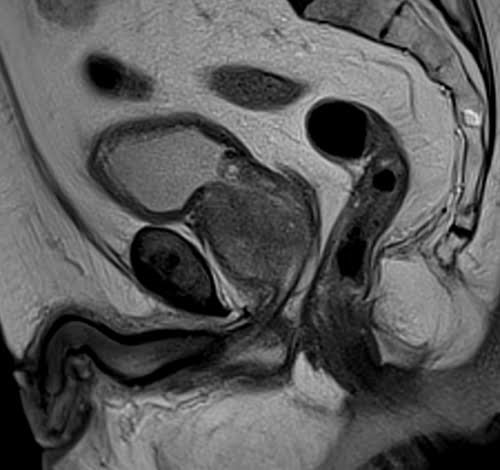

Prostate mri T2 sagittal high resolution images